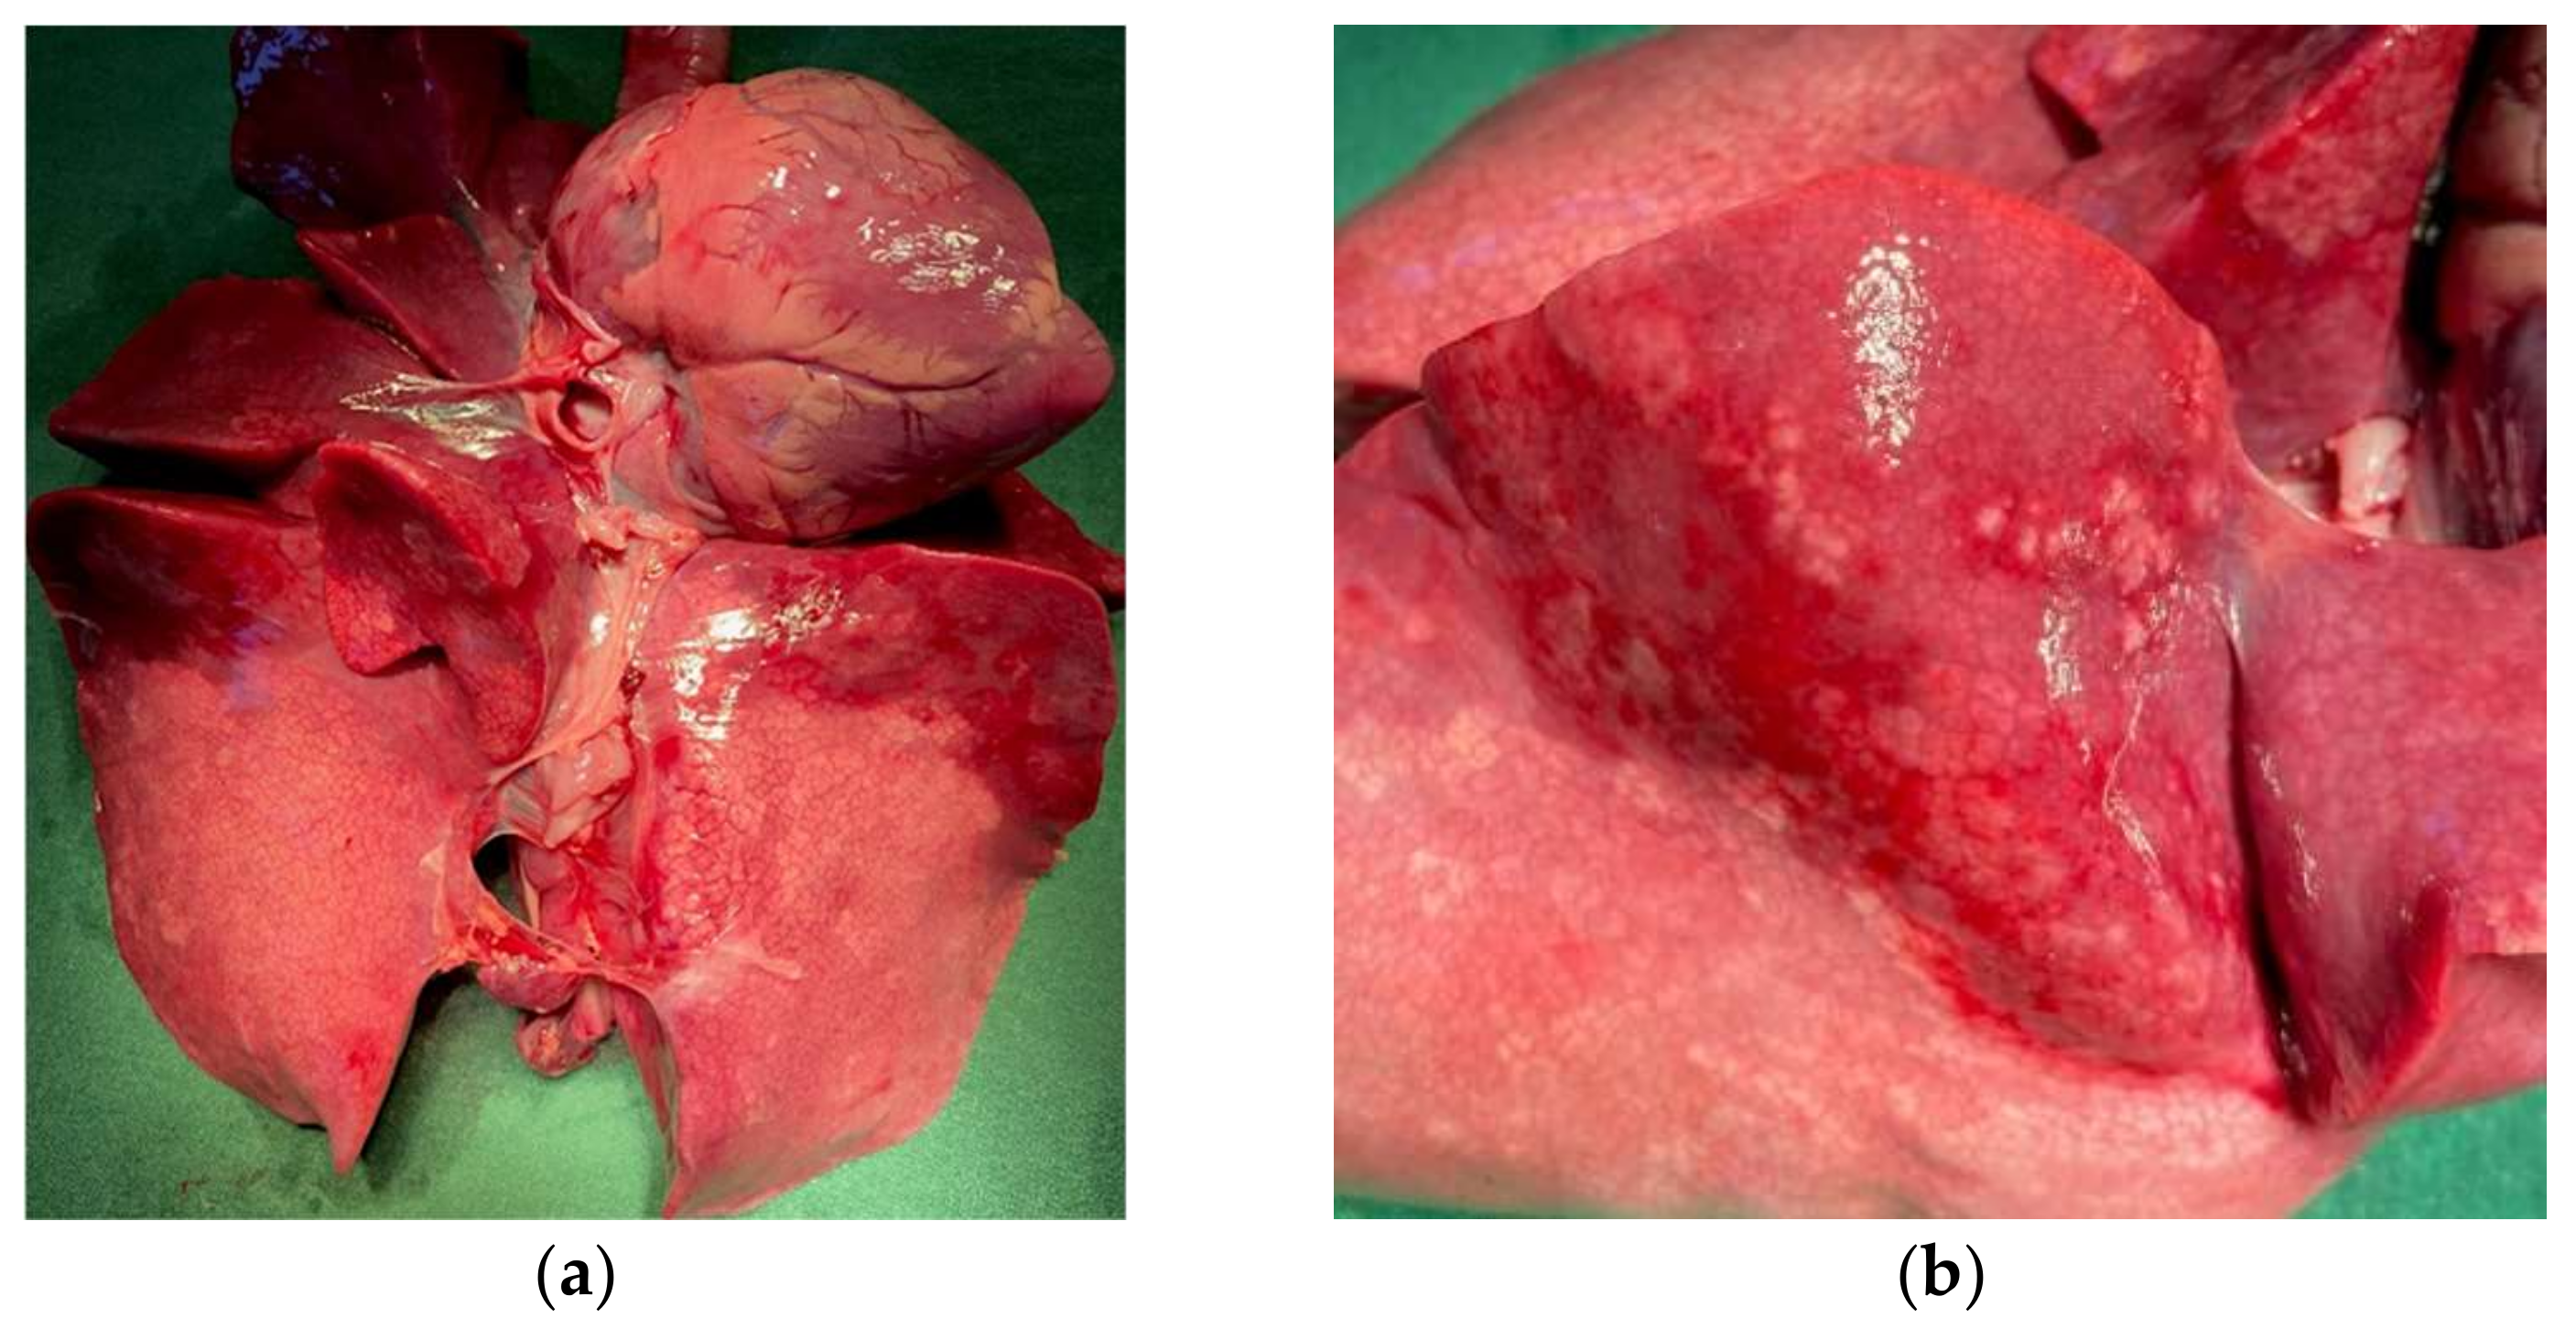

An autopsy was performed on the four deceased T/T lambs. A broad hepatization of lungs probably linked to an infectious pneumonia was particularly observed (Figure 4).

Figure 4.

CCDC65 homozygous affected lamb with lung lesions. (a) heart-pulmonary system of an affected homozygous lamb; (b) magnification of hepatized lobes.

In humans, pathogenic variants in CCDC65 cause Primary Cilia Dyskinesia (PCD), a genetic disorder with autosomal recessive inheritance (CILD27, OMIM#615504). The protein is involved in the assembly of the axonemal nexin-dynein regulatory complex [45]. Axoneme is the axial motor part of cilias composed of nine doublets of microtubules located in the periphery and one central pair complex [40]. Each outer doublet is composed of two tubules (A and B) and is associated with several complexes: outer and inner dynein arms (ODAs and IDs), Nexin-Dynein Regulatory Complex (N-DRC) and Radial Spoke (RS) [40,41,42,43,46]. In particular, the N-DRC is important for the sliding between adjacent outer doublet microtubules to allow cilia motility. The complex is composed of at least 11 subunits shown in C. reinhardtii and conserved among mammals [40,41,42,43]. Among them, variants in one of the three genes: CCDC164 (OMIM #615294 [47]), CCDC65 (OMIM #615504 [44,48]) or GAS8 (OMIM #616726 [49]) have been reported to cause PCD. Bower et al. have demonstrated that the absence of CCDC65 subunit destabilized the association with CCDC164 and GAS8 [45]. Indeed, CCDC65 forms a base plate for N-DRC. Alteration in N-DRC have big consequences for cilia beating leading to the respiratory problems. These three subunits are important for cilia and flagella motility and mucus clearance to eject pathogenic organisms from respiratory tracts. In human, loss-of-function mutations in CCDC65 genes in PCD patients have been identified and are associated with recurrent infectious diseases of the ENT (ear nose throat) sphere as bronchitis, sinusitis, and/or otitis [44,48]. The above clinical profiles are well in line with our observations made in lambs homozygous for the c.521G > T variant in CCDC65. Homozygous lambs have recurrent neonatal respiratory problems. At the autopsy, we particularly observed a broad hepatization of lung lobes resembling infectious pneumonia also associated with growth delay [50]. We hypothesize that, due to the loss of Coiled-Coil domains, the truncated CCDC65 leads to the destabilization of the N-DRC, abnormal cilia beating and impairs the mucociliary clearance resulting in airways obstruction by mucus loaded with pathogens (bacteria, mycoplasma, virus). Pathogens load could depend on the breeding sanitary conditions, individual immunity and veterinary treatment applied, which can explain that the lethality can occur between perinatal and juvenile stages. This is to be connected to the previous observation of a partial homozygous deficit for LDHH6 at the age of genotyping (72 expected and 3 observed) [28]. Indeed, Lacaune candidate rams for genomic selection are genotyped on average at 3 months of age using LD SNP chip indicating that some LDHH6/CCDC65 homozygous lambs have exceeded this age as observed for a female born from our at-risk mating, and a male in a breeding center exceding 5 months of age.